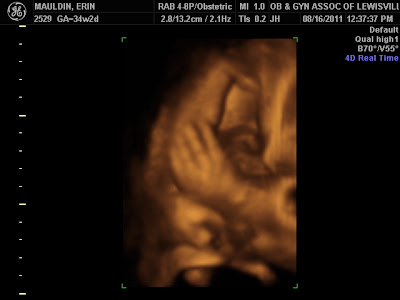

The ultrasound tech said she was smiling in this one. :) You can see the corner of her mouth by her arm. Her arms are crossed and you can see one is balled up in a fist.

You can see the edge of her nose in this one and her fat little cheeks (which were moving in the ultrasound because she was suck and breathing in and out)